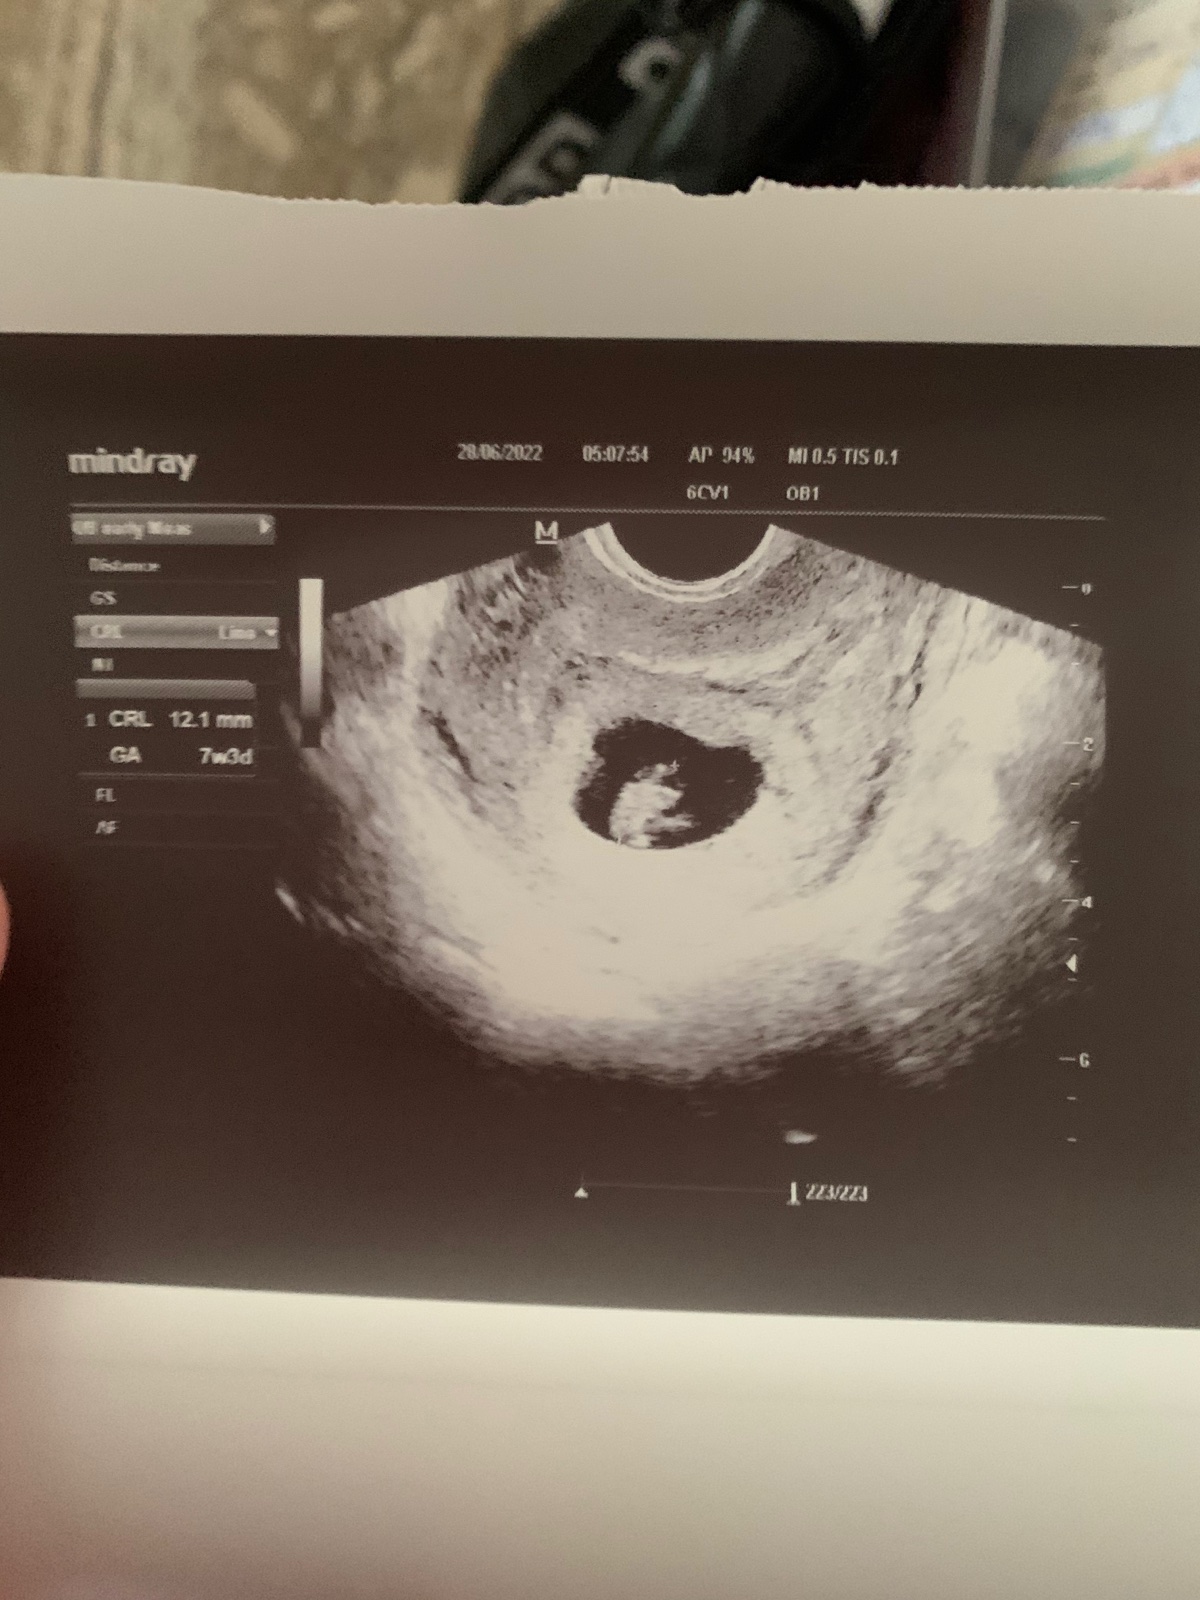

@zuzsat vsetko pekne v limite..iba pepino foteny neskor..